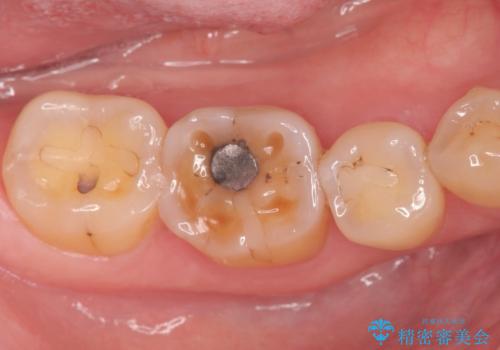

奥歯の深い虫歯

- 以前他院で奥歯にプラスチックの樹脂で虫歯治療を行った患者様です。

かかりつけの歯科医院で虫歯だと指摘され、自費でのゴールドインレーでの修復治療を希望して来院されました。

古い樹脂の詰め物を取り除いたところ、歯の神経と非常に近い状態でした。

万一神経と交通した場合に備え、唾液が入らないようにゴムのシートで防湿(ラバーダム防湿)を行い虫歯除去を行いました。

幸い神経とは交通せず、処置後の神経症状もありませんでした。

ご希望に沿って、ゴールドインレーにて治療を行いました。

- PGA(ゴールド)インレー 6.6万円 × 2本費用は治療当時の料金となります